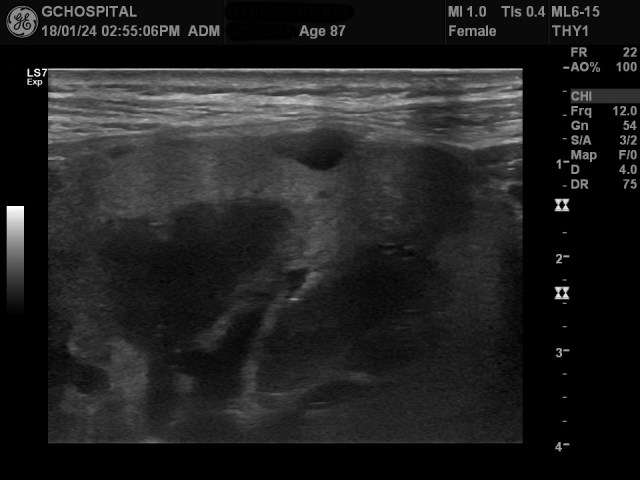

문제는 맨 처음에 봤던 신장 윗부분에 있던 단순낭종입니다. 분명 8미리정도 크기의 단순낭종이 보이고, 그 위에는 다른 낭종이 없었는데, 선형탐촉자로 확인해보니, 앞서 보였던 8미리 크기의 단순낭종의 윗부분에 이보다 크기가 훨씬 더 큰 낭종성 병변이 보이는 겁니다. 뭔가 상황이 이상하게 돌아가고 있습니다. 이 외에도 더 작은 낭종들이 추가로 보이고 있습니다.

분명히 신장의 윗쪽부위도 확인했다 생각했는데, 이런 정도로 큰 낭종이 보이지 않았기에 이상해서 해당 낭종을 더 자세히 들여다보았는데, 더 황당하게도 이게 낭종이 아닌 비교적 고형성 종괴였던 겁니다. 크기는 2.5센티미터 정도였습니다.